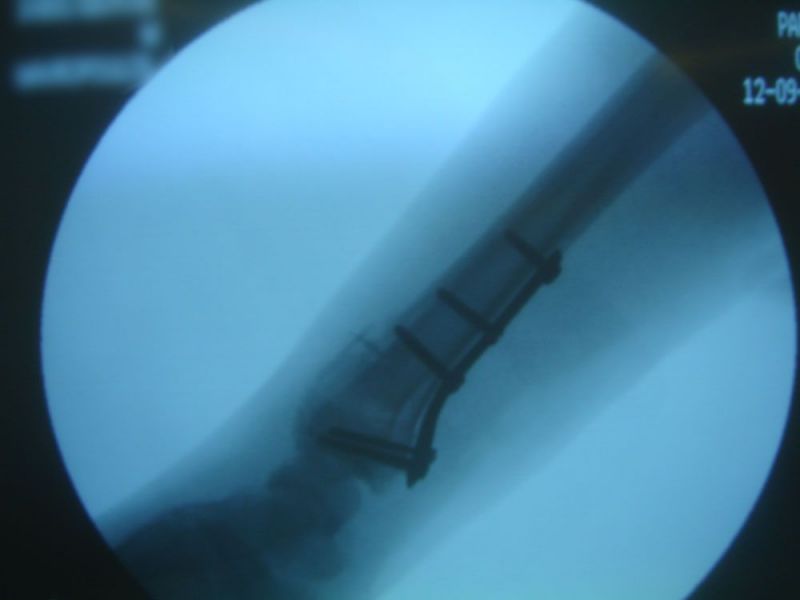

Management

Its treatment could be the closed reduction with the use of a cast. If the reduction is not satisfactory or there is a loss of reduction, surgical treatment has to take place.

Distal radius fracture-open reduction internal fixation (lateral view)